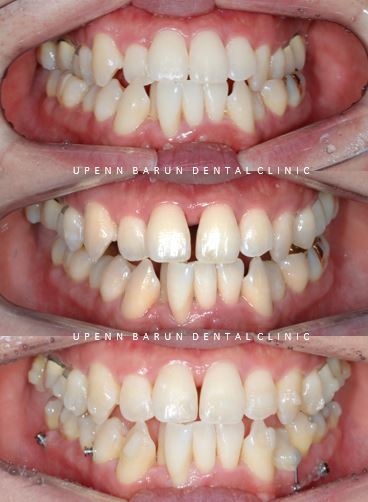

Case 1

치료기간 22.3 ~ 23.4 , 현재 인비절라인 진행중

위 사진은 환자분의 좁은 악궁을 넓히기 위해

악궁확장장치인 'Marpe'를 사용한 사진입니다

장치를 장착하고 약 한달 후

노란색 화살표와 같이 정중구개봉합선이 분리되며 앞니가 벌어졌고,

그 공간을 활용하여 인비절라인으로 치아를 재배열한 사진입니다.

점점 갈수록 악궁이 확장되는것이 보이시나요?

상악이 Δ와 같이 좁은 모양에서 넓은 U 모양으로 변화되었습니다.